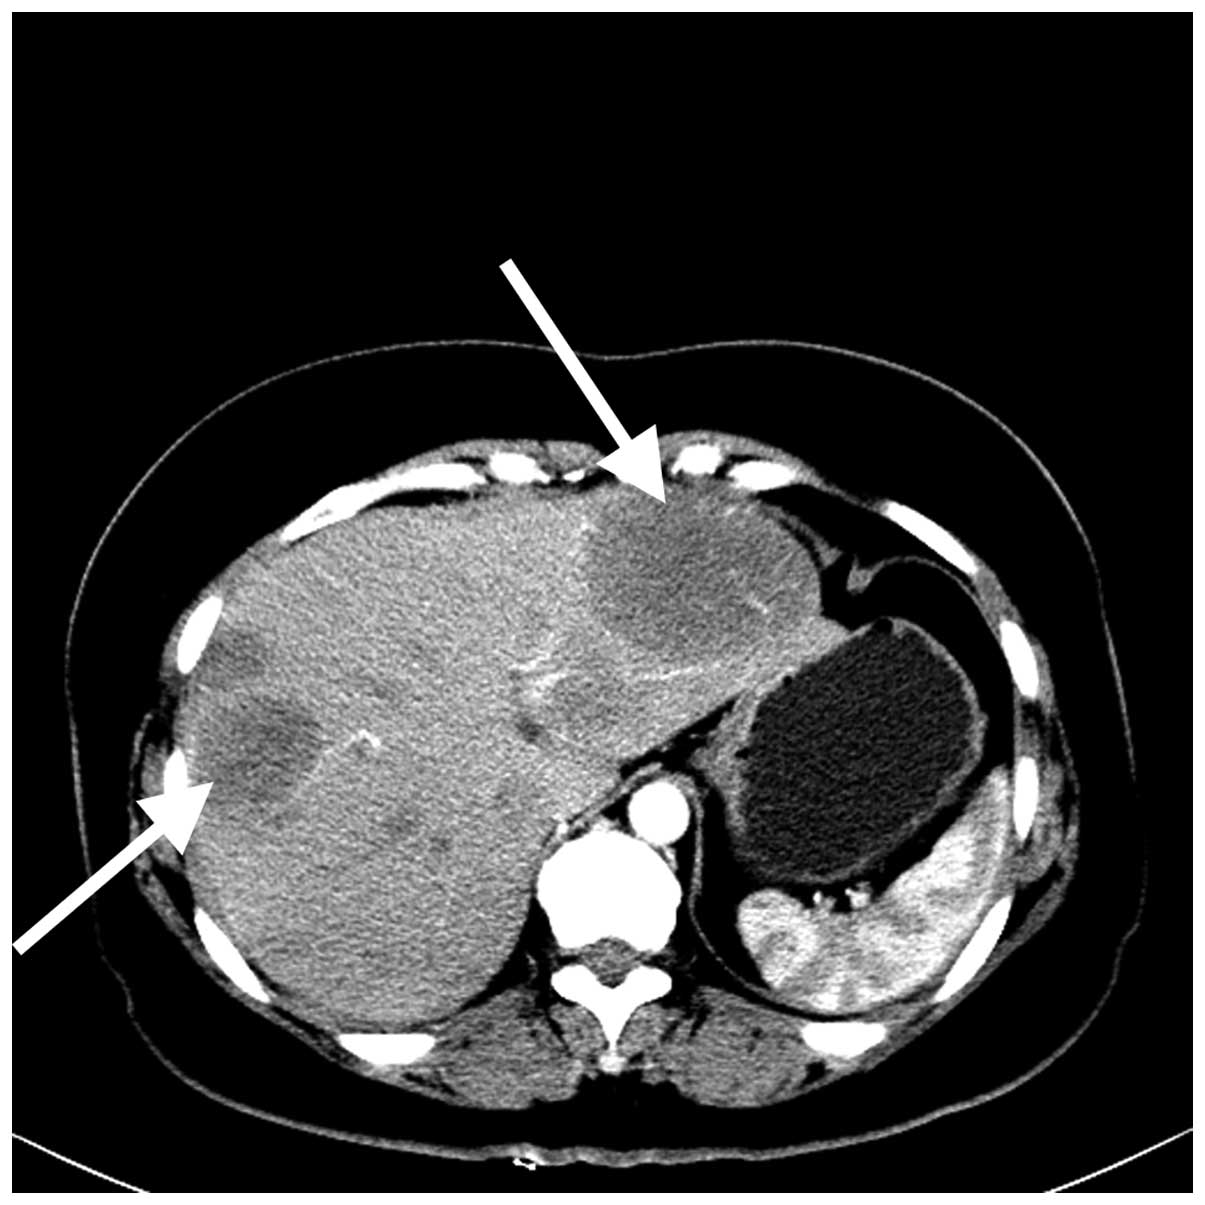

Подкожные метастазы при раке легких - фото презентация